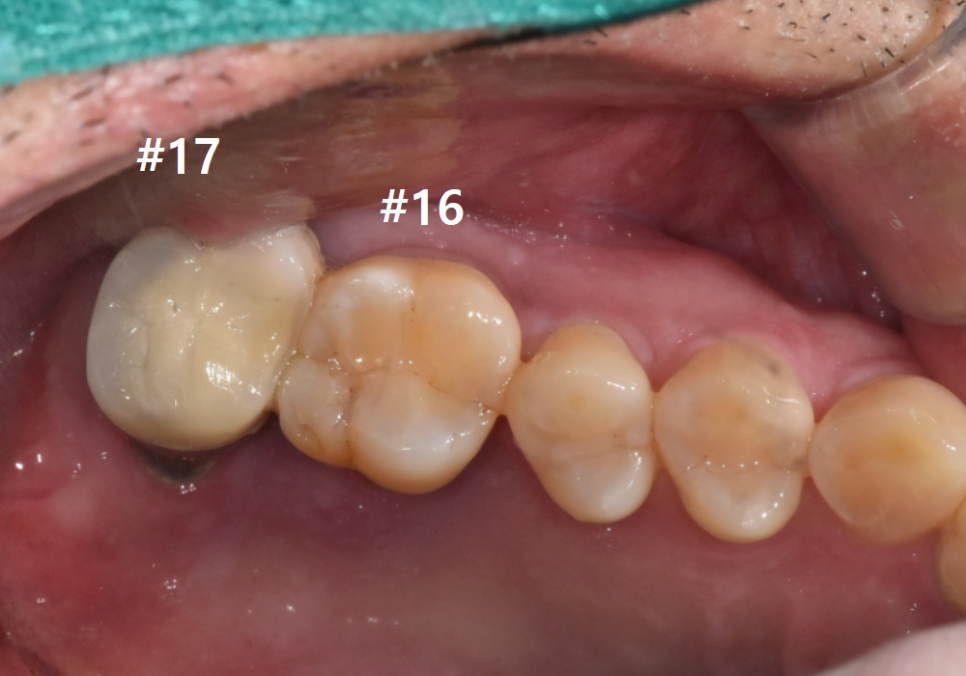

얼마 전 오른쪽 위 어금니가

씹을 때마다 아프고 흔들린다며

내원하신 환자분의 사례입니다.

보시면 오른쪽 위 어금니(#16)는

뼈 흡수가 한눈에 봐도

심각하게 진행된 모습입니다.

그런데 그 뒤에 있는 치아인 #17은

앞에 치아에 비해 뼈가 크게 녹아 보이지 않으시죠?

사실 이 #17 치아도 상태가 결코 좋지 않았습니다.

겉보기엔 멀쩡해 보이는데

왜 좋지 않다고 말씀드리는 걸까요?